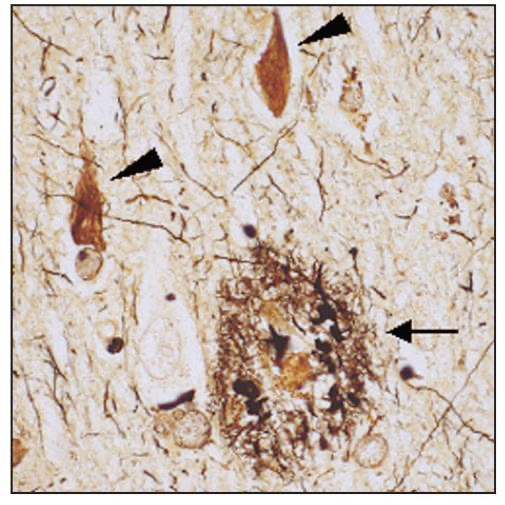

阿尔茨海默病最典型的症状,就是大脑里出现两个标志性病理特征:一个是Aβ蛋白酶沉积形成的老年斑,还有一个是Tau蛋白过度磷化形成的神经纤维缠结。一些看似健康的人,什么典型症状都没有,但其实大脑里已经出现了病变。

阿尔茨海默病患者主要神经病理学现象,箭头所指的是“淀粉样斑块”,三角箭头所指的是Tau蛋白异常聚集形成的“神经原纤维缠结”

宋伟宏说,大脑里发生的病理变化,是在出现症状之前的五年、十年甚至二十年就开始启动了。这个过程可能会持续5到20年,但遗憾的是,我们没有一个很好的方法来检测:到底什么时候发生了变化。